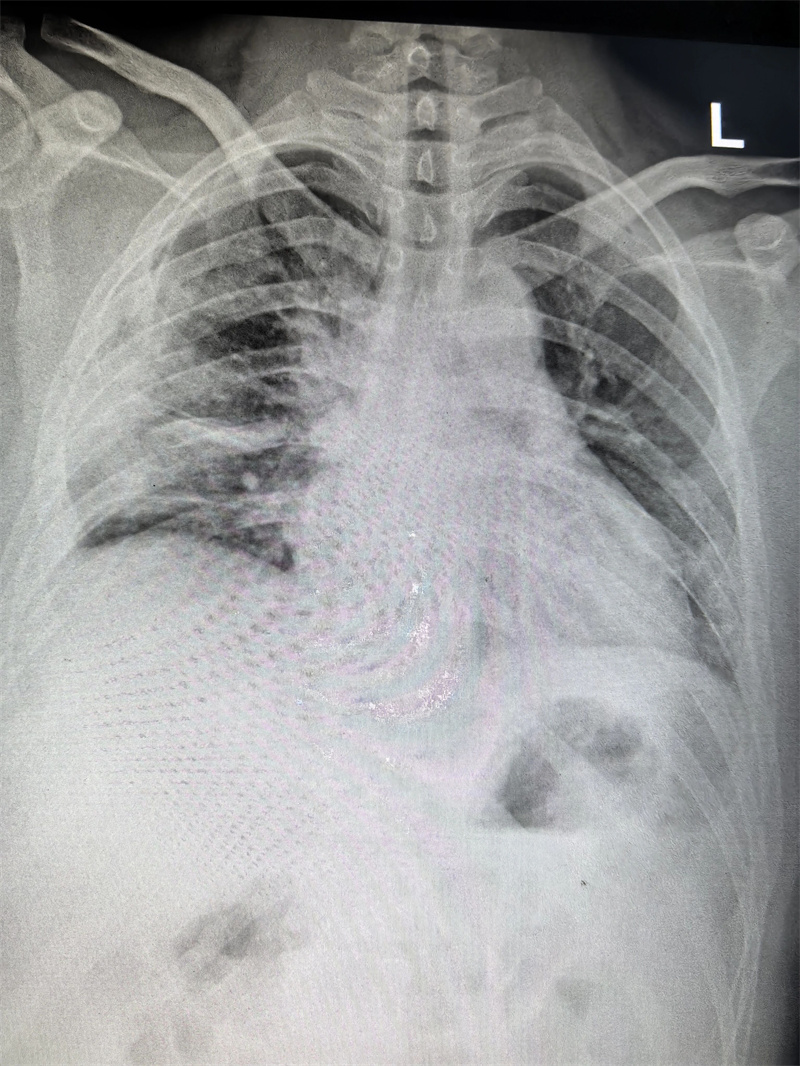

四个月前,23岁的小雨(化名)因胸闷前往医院就诊,CT检查结果显示右侧胸腔靠上位置出现包裹性脓胸,并进行穿刺检查,最终确诊为结核性包裹性脓胸,这个消息让小雨和家人陷入了深深的焦虑之中。

看着日益憔悴的小雨,医生建议手术治疗。术前,田子刚主任和宋巍峰医生在全面评估了小雨各项指标后,确定符合手术标准,便与麻醉科以及护理团队紧密配合,为小雨实施胸腔镜下胸膜剥脱术。

小雨的手术切口很小,大约只有4厘米,出血量也仅100ml,这对小雨的愈后起到了很好的作用。术后,小雨在医护人员的精心照料下恢复得很快,于10月24日顺利出院。